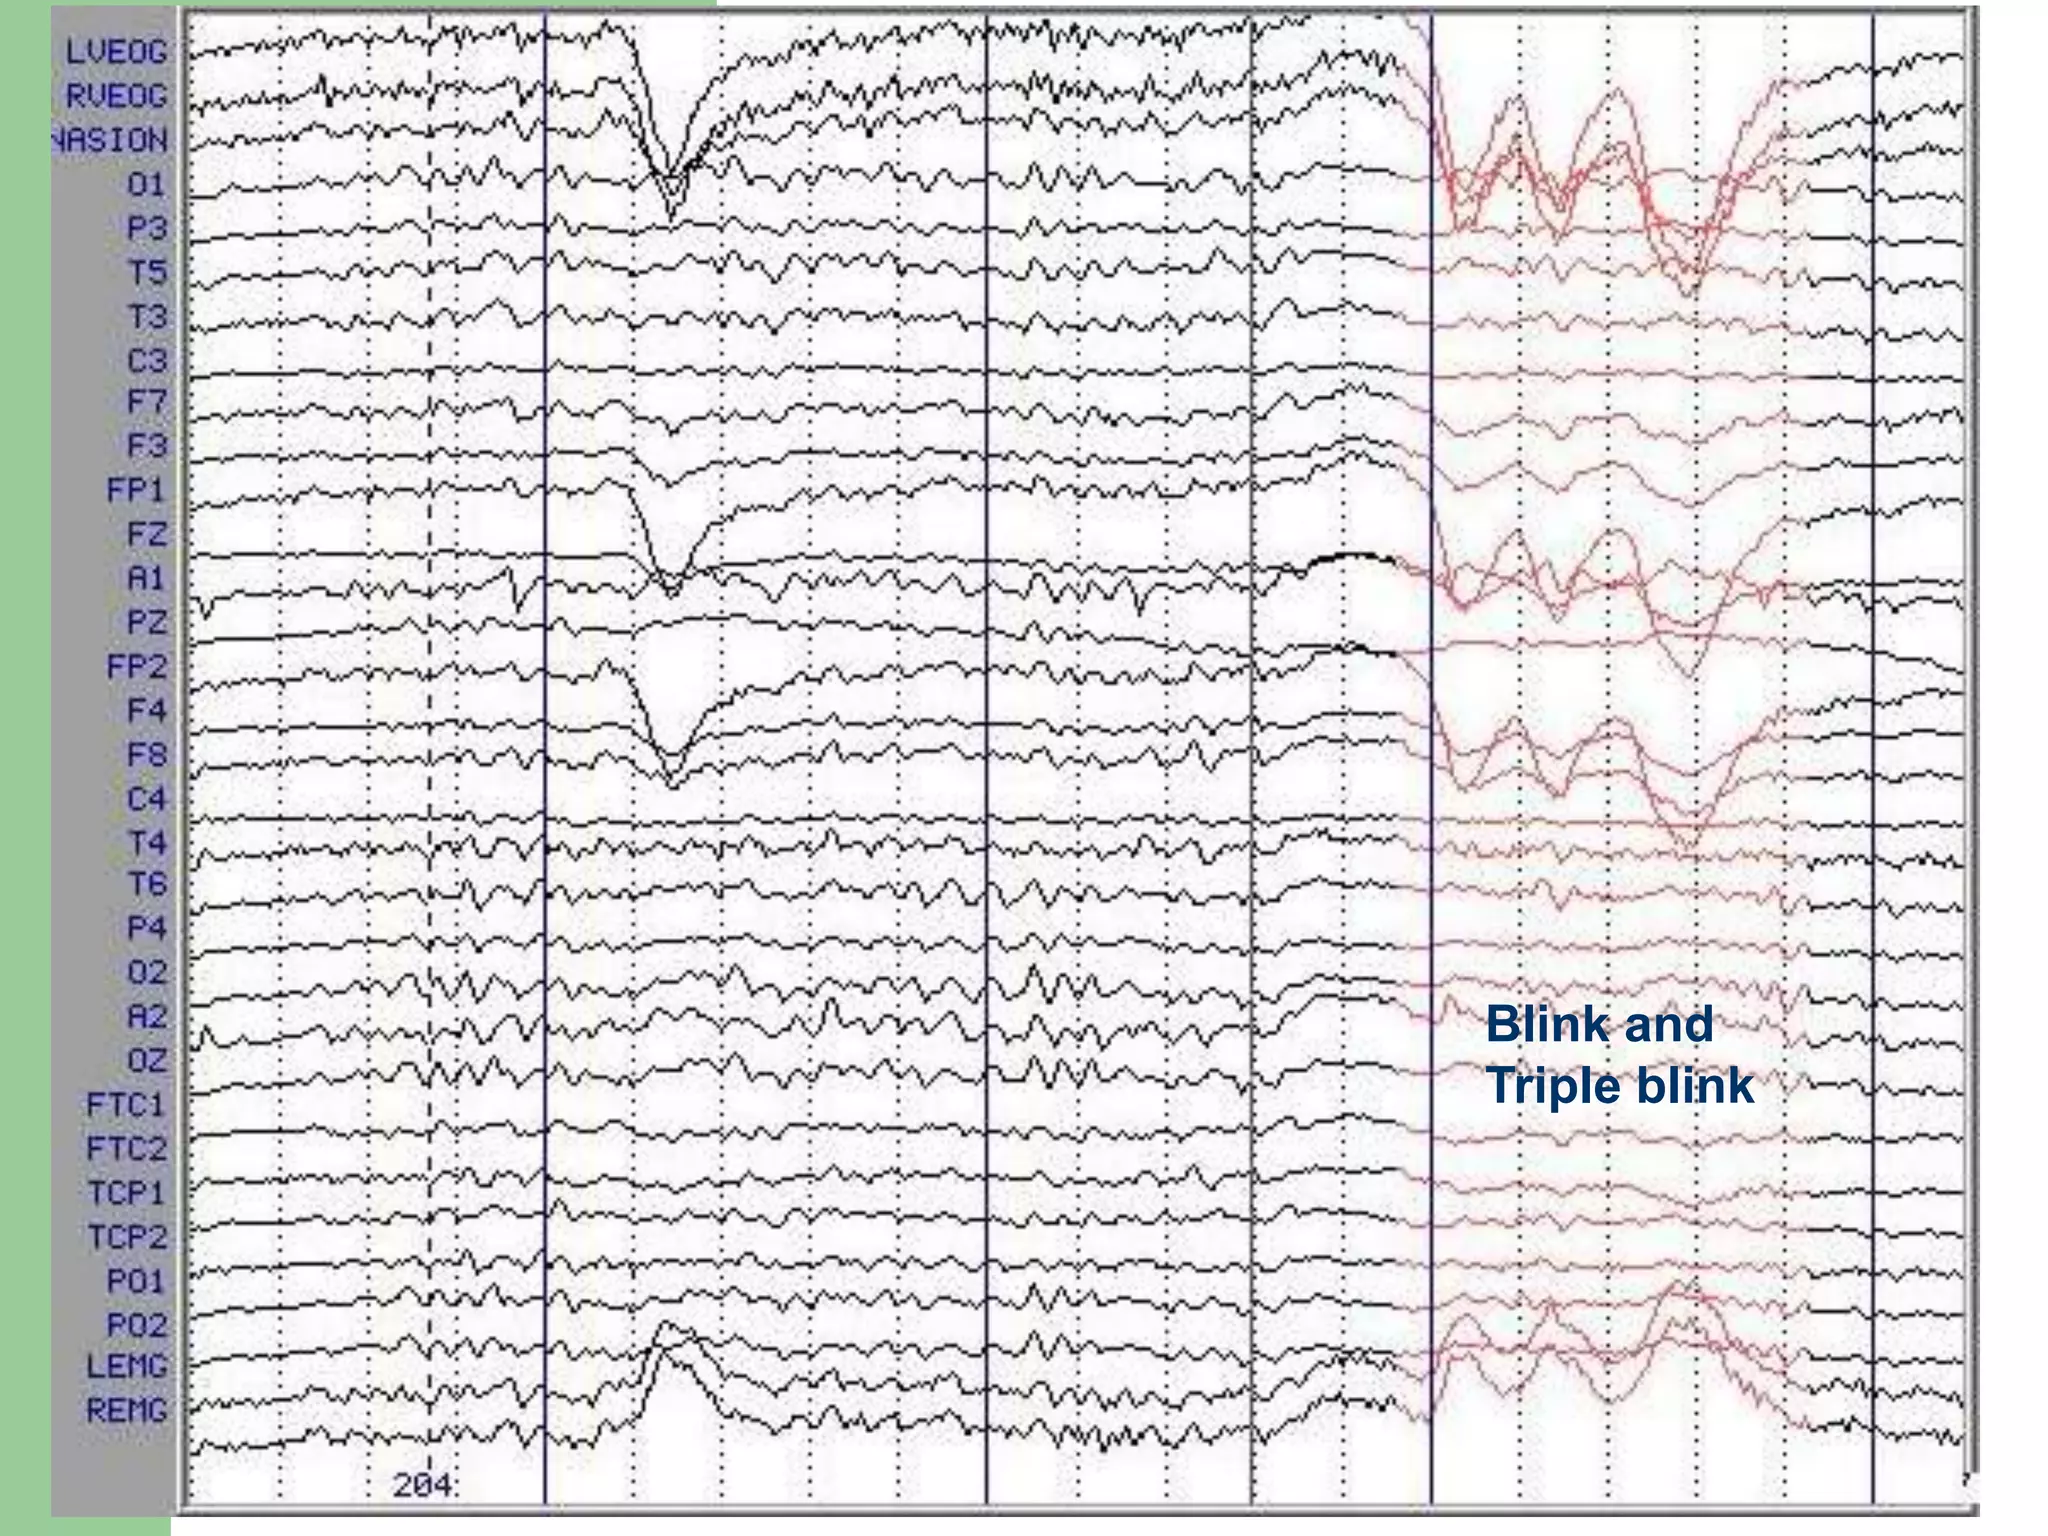

Blink and

Triple blink